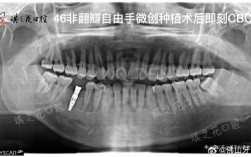

- 牙齿数量和形态: X光片(尤其是全景片)可以清晰显示所有牙齿(包括尚未萌出的智齿、埋伏牙、多生牙、缺失牙)的位置、数量、形态和发育情况,肉眼只能看到已经长出来的牙齿,看不到牙根、牙槽骨以及颌骨内部的情况。

- 牙根情况: 可以观察每颗牙齿的牙根长度、形态(是否弯曲、短小、有无吸收)、位置以及牙根之间的距离,牙根是牙齿移动的基础,了解其状况至关重要。

- 牙槽骨状况: X光片(尤其是全景片和根尖片)可以评估牙槽骨的高度、厚度和密度,牙槽骨是支撑牙齿的“地基”,其健康状况直接影响牙齿移动的可行性和稳定性,牙槽骨吸收严重可能会限制牙齿移动或增加风险。

- 保护重要解剖结构: 了解牙根与下颌神经管的位置关系(全景片或CBCT),可以避免在移动下颌后牙时损伤神经,上颌窦的位置信息也有助于评估上颌后牙移动的安全范围。